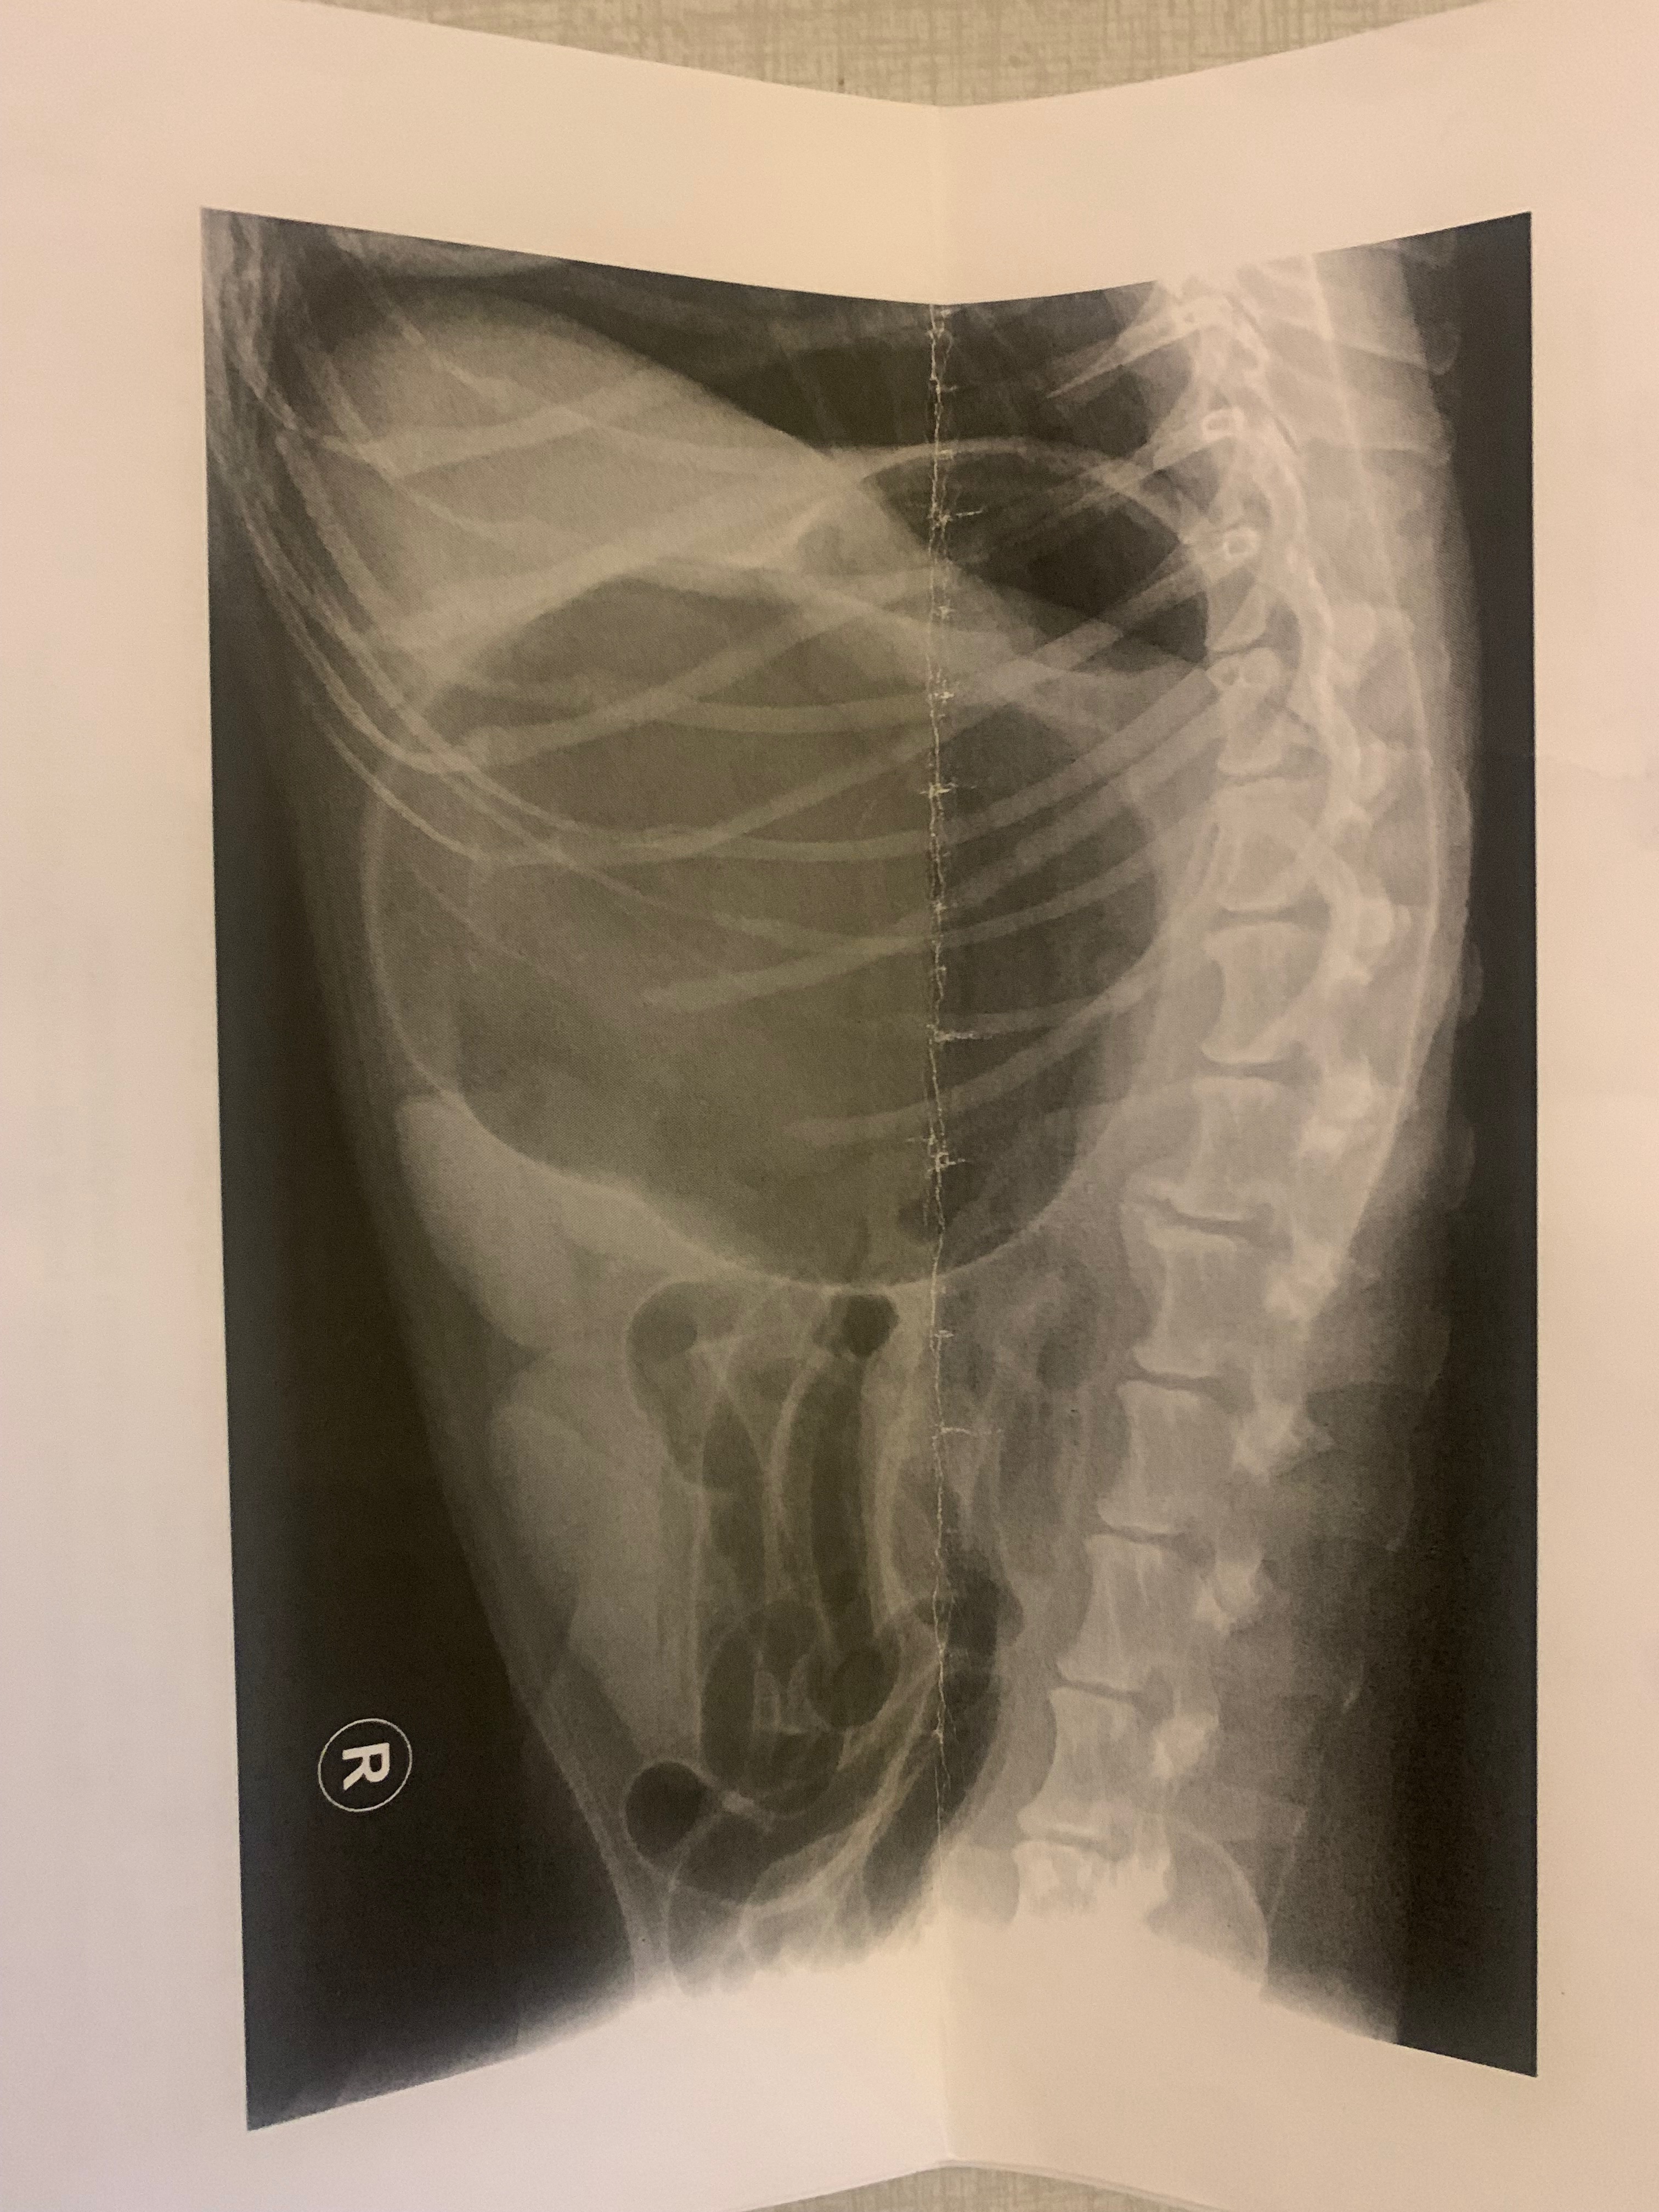

Maya experienced a condition called GDV, also known as bloat. Her stomach filled with gas and twisted, cutting off blood flow to vital organs. GDV is a sudden and life-threatening condition that required immediate surgery to save her life, so we moved forward with treatment right away, but the cost of the surgery and hospitalization was more than we could manage on our own.